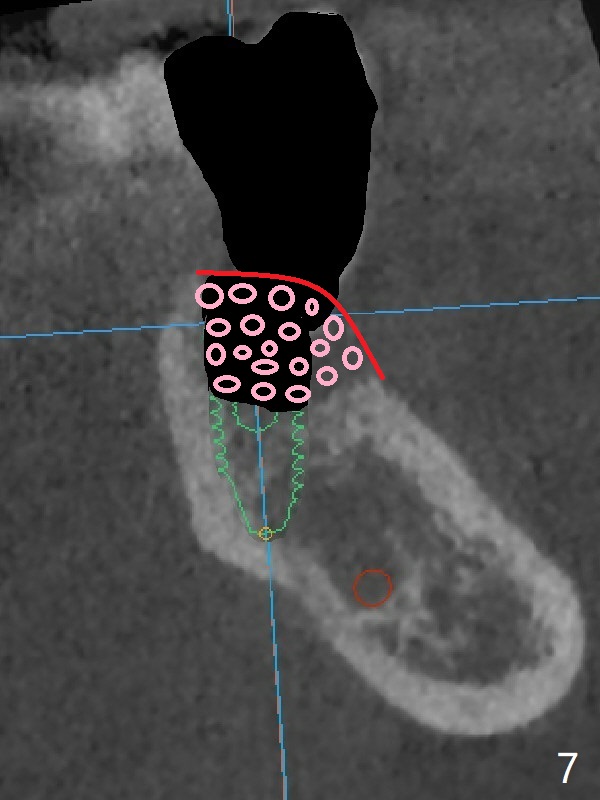

In contrast without implantation after extraction (Fig.6 (ignore green)), the socket may be grafted (Fig.7 pink circles) and covered by PRF membrane (red line). Due to the large socket with severe buccal defect, the graft is more likely to be lost (Fig.8). Several months later, an implant to be placed (Fig.9 green) will be short with unfavorable crown/implant ratio.